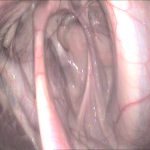

- Endoskopie (Spiegelung) der oberen und unteren Atemwege mit der Möglichkeit zur Entnahme von Proben zur weiteren Differenzierung der Erkrankung

Entnahme von Tracheobronchialsekret

- Durchführung einer bronchoalveolären Lavage

- Entnahme von Gewebeproben